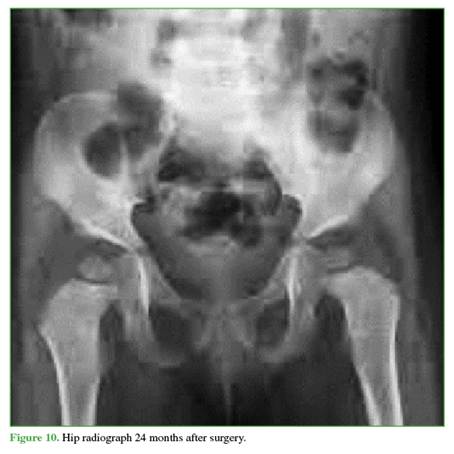

Figures 9 and 10 show the imaging follow-up at 6 and 24 months after removal of the osteosynthesis material.